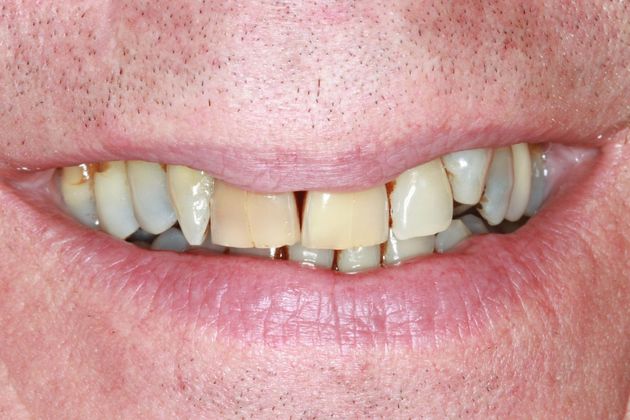

Center for Dentistry

At Center of Dentistry, our dentists favor a patient-friendly approach to cosmetic and comprehensive dentistry. Our highly trained staff will go the extra mile to make you feel at ease. Our dentists are affiliated with professional organizations including: